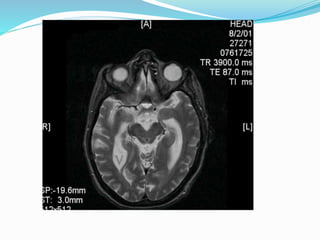

Magnetic Resonance Imaging

 Temporal horns out of proportion to hippocampal atrophy

 MRI provides additional physiologic information on NPH

 T2-weighted images, regions of moving CSF demonstrate

no signal, instead of the increased signal observed in slow-moving

CSF,

 CSF flow studies- jet of turbulent CSF flow may be

observed distal to the aqueduct

 Cine phase-contrast MRI quantifies CSF flow in terms of

stroke volume

 - significant corelation to shunt responsiveness